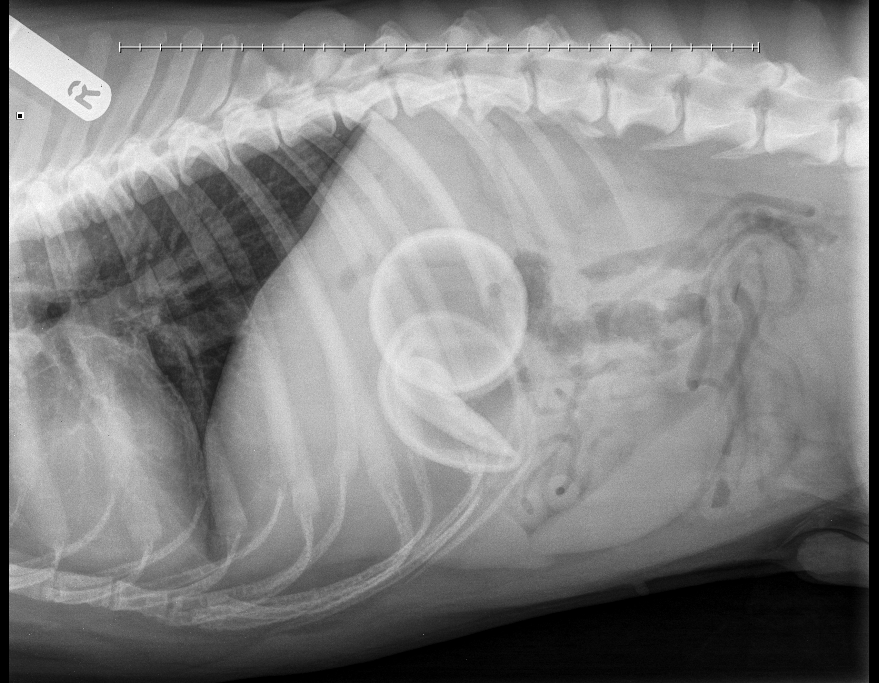

from sashvets.com

Beware of tennis balls SASH Vets